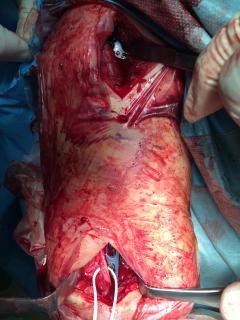

Περίπτωση 4ου ασθενούς

Τα εν λόγω κατάγματα είναι αρκετά συνηθισμένα και συχνά συμβαίνουν μετά από τροχαία ατυχήματα ή πτώση από ύψος. Παρατηρείται εξαιρετικά μεγάλη ποικιλία στη μορφή τους, κατα κανόνα όμως είναι σοβαρά και πολλές φορές ανοικτά – δηλ με τραύμα στο σημείο του κατάγματος – κάτι που αυξάνει τον κίνδυνο λοίμωξης και επιβαρύνει την πορεία της θεραπείας. Στα κατάγματα των άνω άκρων ενδέχεται να υπάρξει και τραυματισμός νεύρων, που χρειάζεται επίσης αντιμετώπιση.

Οπως και άλλοι εξοικειωμένοι χειρουργοί διεθνώς, χρησιμοποιώ τεχνικές ελάχιστης παρέμβασης (Minimal Invasive Surgery), δηλαδή μικρές τομές, επειδή έτσι το χειρουργικό τραύμα είναι ελάχιστο, με αποτέλεσμα ταχύτερη επούλωση. Ταχύτερη πώρωση των καταγμάτων, ταχύτερη κινητοποίηση.